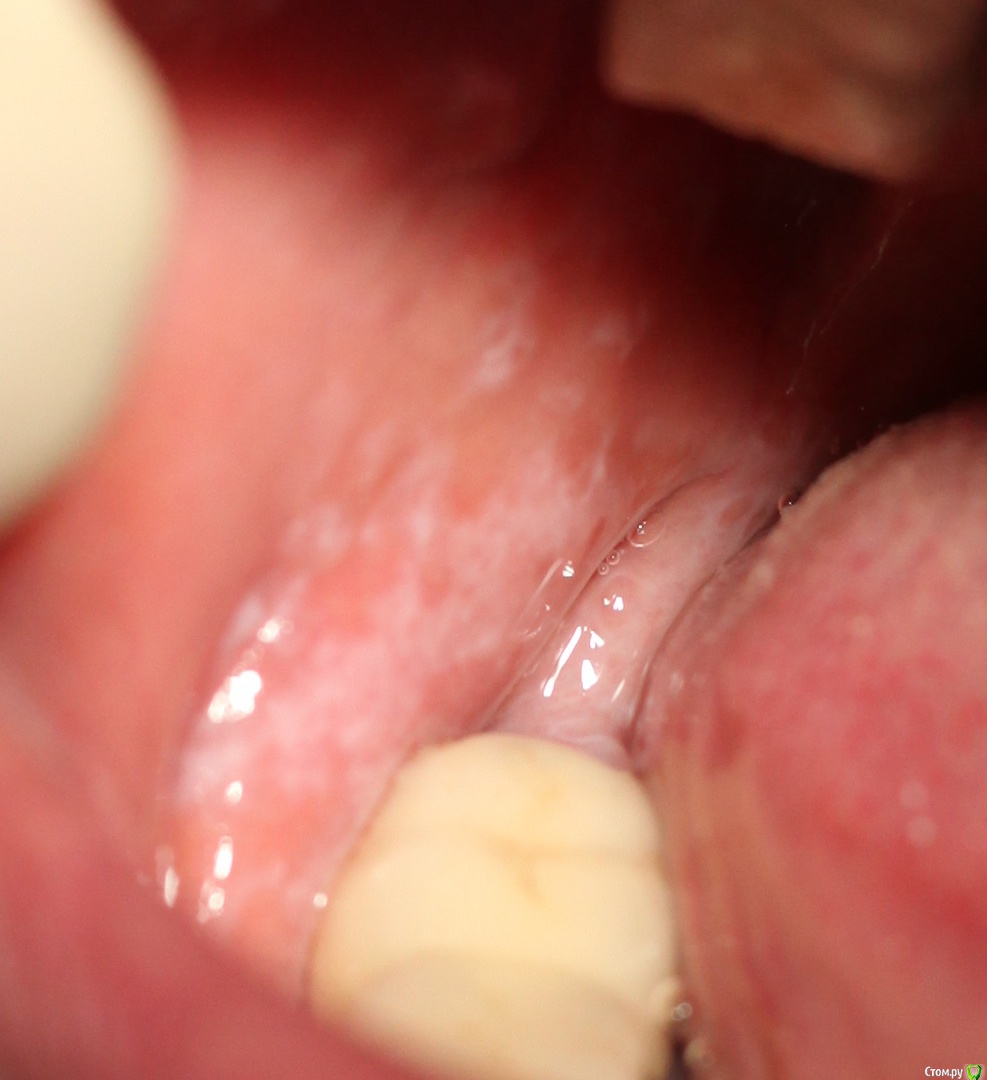

Dr.Yuliya Опубликовано 4 мая, 2017 Поделиться Опубликовано 4 мая, 2017 Коллеги помогите. Пациентка 57 лет. Предположила, что это лейкоплакия. Подобные пятна и с право и с левой стороны, локализация аналогичная. В анамнезе курение, не санирована.Отправила на Вучетича университет на консультацию. Какие у кого предположения? Ссылка на комментарий

Pan Опубликовано 5 мая, 2017 Поделиться Опубликовано 5 мая, 2017 Визуально (без сбора анамнеза) похоже на лейкоплакию. Ссылка на комментарий

1586Doc Опубликовано 5 мая, 2017 Поделиться Опубликовано 5 мая, 2017 плохо видно картинку. Возможно кпл Ссылка на комментарий

StomV Опубликовано 15 мая, 2017 Поделиться Опубликовано 15 мая, 2017 Сетку Уикхема напоминает. Ссылка на комментарий